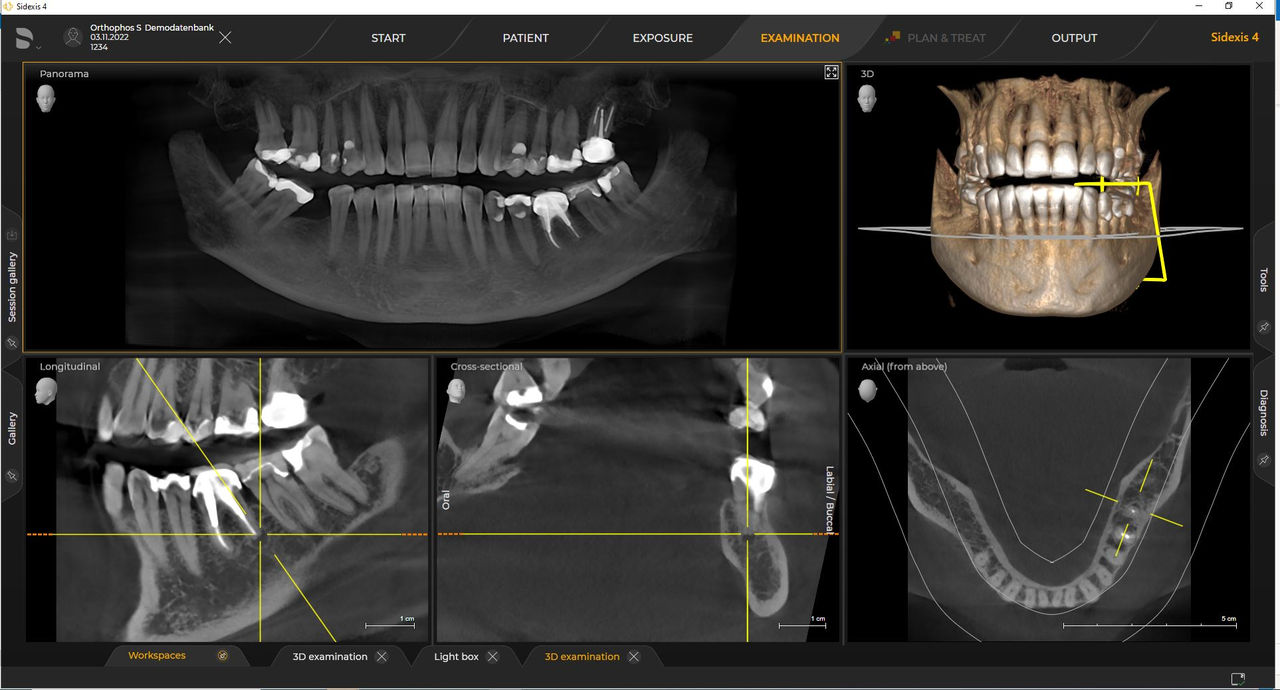

Con el modo de dosis baja inteligente 3D, obtiene imágenes 3D en el rango de dosis de una imagen radiológica 2D. En el modo HD (hasta 1400), las imágenes individuales se obtienen durante una única rotación y se convierten en un volumen 3D con hasta 80 μm para imágenes de bajo ruido en alta resolución.

Las unidades de radiología de Dentsply Sirona funcionan exclusivamente con Sidexis 4. Sin embargo, la migración de datos de Sidexis XG a Sidexis 4 es muy fácil. Sidexis 4 permite una experiencia digital completa con las últimas herramientas